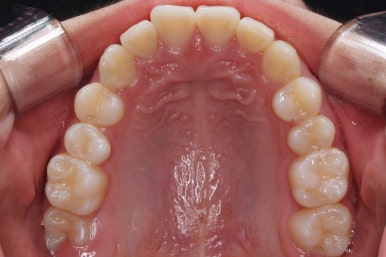

부산치아교정잘하는곳 처음 오셨을 때의 입안 모습입니다.

맨 우측 밑에 사진을 보시면 이가 하나 더 나와야 할 자리에(화살표) 앞뒤로 치아가 쓰러지면서 자리를 거의 없애버렸습니다.

따라서 이가 나올래야 나올 수가 없는 상태였습니다.

왼쪽 맨 위 사진을 보시면 아래 치열의 중앙이 한 쪽으로 쏠린 것을 알 수 있는데요. 역시 치아가 나올 자리가 없어지면서 치열이 쏠러버렸다는 것을 알 수 있습니다.